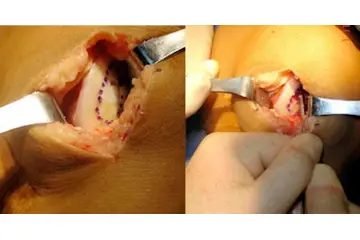

Kıkırdak dokusunun hasar görmesi durumunda uygulanabilecek çeşitli tedavi yöntemleri bulunmaktadır. Bu tedaviler arasında fizik tedavi, ilaç tedavisi (ağrı kesiciler ve anti-inflamatuar ilaçlar), enjeksiyonlar (kortikosteroid veya hyaluronik asit) ve ileri vakalarda cerrahi müdahaleler yer alabilir. Cerrahi tedaviler arasında artroskopi, mikrokırık cerrahisi ve kıkırdak nakli gibi yöntemler bulunur.